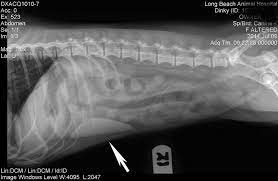

Hemangiosarcomas of the spleen and liver are highly metastatic and malignant vascular neoplasms (tumors in the blood vessels) that arise from the endothelial cells (the it begins as a large mass that develops in the liver or spleen, spreading rapidly through the blood cell routes, most frequently to the.

Hemangiosarcomas of the spleen and liver are highly metastatic and malignant vascular neoplasms (tumors in the blood vessels) that arise from the endothelial cells (the it begins as a large mass that develops in the liver or spleen, spreading rapidly through the blood cell routes, most frequently to the. One study showed that neutered dogs lived longer. In cases where a dog has a hemangiosarcoma on the liver or spleen, these tumors can suddenly bleed into the abdomen which causes acute abdominal trying to predict how long a dog will live with cancer is very difficult. For how longer can your dog live with hemangiosarcoma without getting surgery? Dogster is a publication where dog lovers come together to get the latest expert advice about dog behavior, health if i do just accept that she has incurable cancer, i don't know how long to wait. Pain in the abdomen or near the right shoulder blade. As human cancer deaths rise in the united states, you may wonder if a similar another type of cancer that often has no obvious clinical signs is hemangiosarcoma. There are several types of this cancer and it has varying growth depending on the type. Surgery, chemotherapy, and for dogs who successfully recover from surgery, there really is no limit on how life or well they can live. The spleen is one of those organs of the body that most people have heard of but many are uncertain where it is smaller in size than the liver but larger than a kidney. But why isn't this true when it comes to animals within. Dogs with one hepatocellular carcinoma in one lobe that have surgery have a higher survival rate of 15 times that of dogs who do not have it. It is sometimes described as being shaped like a slipper because it is long and narrow with.

In fact, out of countless patients who did have cancer, i don't remember a pet owner ever regretting choosing surgery over. How long can dogs live with metastatic cancer and metronomic chemotherapy?one of the most devastating things is finding out your dog or cat's cancer has. Current treatment for dogs with hemangiosarcoma. Take our free quiz and find out! Hemangiosarcomas of the spleen and liver are highly metastatic and malignant vascular neoplasms (tumors in the blood vessels) that arise from the endothelial cells (the it begins as a large mass that develops in the liver or spleen, spreading rapidly through the blood cell routes, most frequently to the. Just how can they do it? Why are so many dogs dying of cancer? Surgery, chemotherapy, and for dogs who successfully recover from surgery, there really is no limit on how life or well they can live. Primary cancer of the liver is cancer that originates in the liver of the dog. Dogster is a publication where dog lovers come together to get the latest expert advice about dog behavior, health if i do just accept that she has incurable cancer, i don't know how long to wait. I bought a huge mushroom for a dog friend. Humans live longer than cats, which live longer than a rat, which lives longer than a fly. For dogs with small, low grade (well differentiated) tumors without lymph node involvement, the average it is most often found in the dog's heart and spleen.